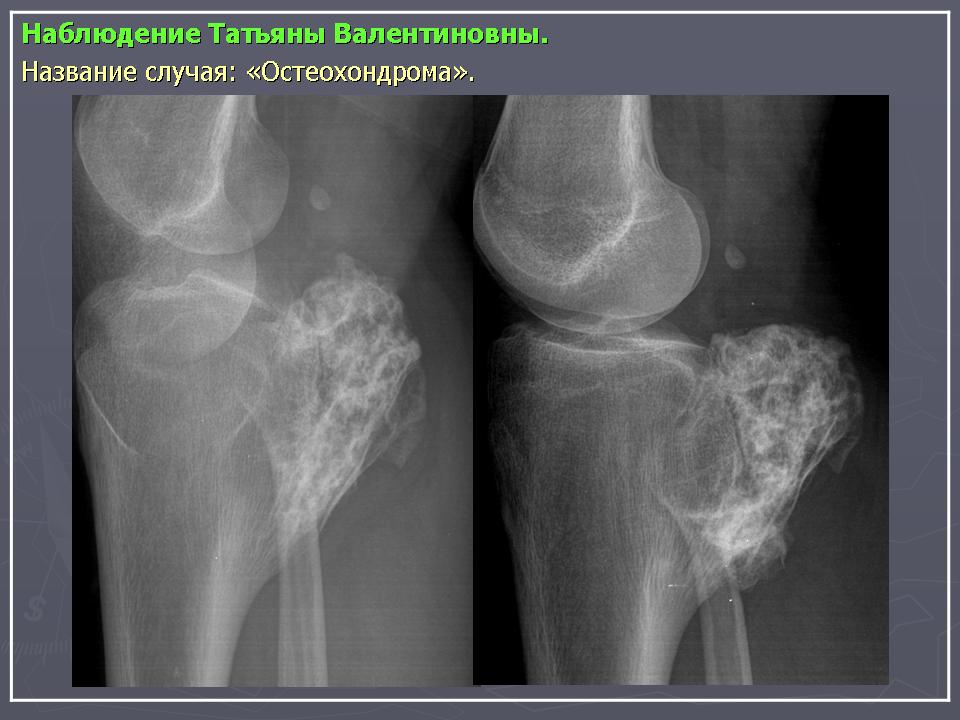

Остеохондрома (костно-хрящевой экзостоз).

Наблюдения коллег.